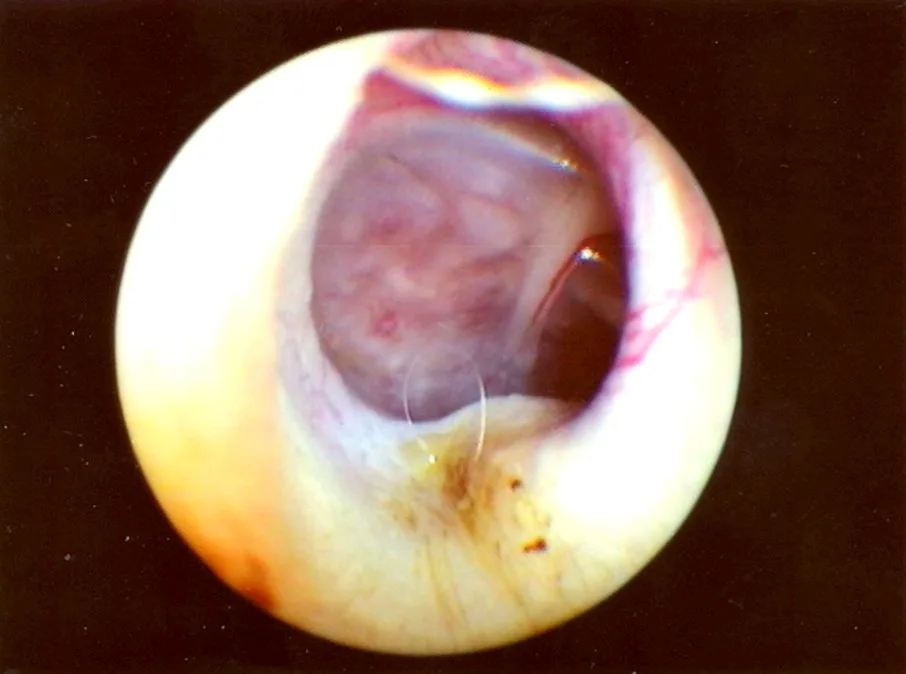

Chronic ear disease that has led to thickening and scarring of the eardrum (Figure 4)

FIGURE 4 Normal right eardrum (left). Fibrous connective tissue covering the left eardrum (tympanosclerosis) (right).